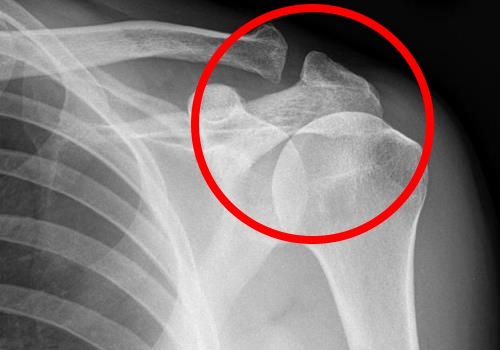

Врач может провести пальпацию пораженной области, что может вызвать у пациента острую боль. Однако самым информативным методом остается рентгенография. Во время этого исследования специалист может увидеть наличие патологий и определить стадию их развития.